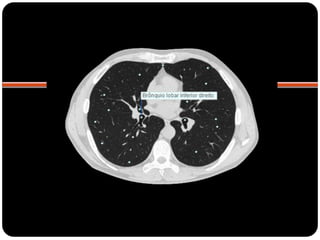

Atelectasia lobo

inferior direito